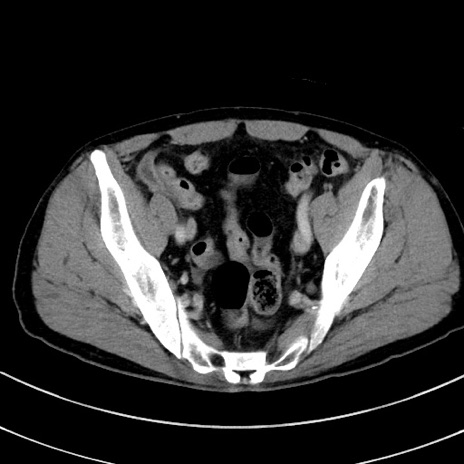

冠状断像

症例8(横断像)

【症例】 60歳代男性

【主訴】 黒色吐物

【現病歴】 4日前から嘔気自覚、2日前の朝食後にも嘔気あり、自分で手で嘔吐反射起こし嘔吐したところ血が混ざっていたため受診。

【既往歴】 5年前汎発性腹膜炎を伴う急性虫垂炎で手術、高血圧、前立腺肥大症、高脂血症

【身体所見】 腹部正中に手術癩痕あり 腹部平坦・軟圧痛なし膨満感あり

【データ】WBC 8400、CRP 4.54